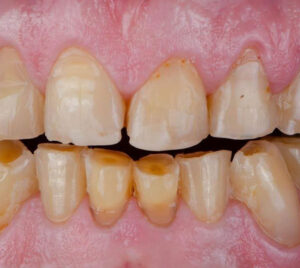

咬耗症は、歯と歯、または歯と食べ物との接触によって歯のかむ面がすり減っている状態です。

硬い食べ物の頻繁な摂取や強い咬合力などが主な原因となっており、特に食いしばりや歯ぎしりの習慣がある方は、咬耗の進行が加速する傾向があります。

ただし、咬耗症は必ずしも病的とは限らず、年齢を重ねればほとんどの人にある程度見られる自然な現象でもあります。

問題となるのは摩耗の程度と症状の有無であり、咀嚼機能や審美性に影響を及ぼす場合には治療が必要となりますが、見た目上特に気にならず、症状がない摩耗については経過を観察しても問題ありません。

治療としては、摩耗が大きくかみ合わせに影響している場合には、レジンで欠損部を補修し形態を補います。

また、歯ぎしりや食いしばりが原因の場合は、ナイトガードの装着によって進行を予防します。

生活習慣の見直しと予防措置を組み合わせることが、咬耗症の管理において重要です。

摩耗症は、咬合以外の力で歯がすり減っている状態です。

原因としては、不適切な歯ブラシの使い方や、パイプをくわえる習慣、管楽器の演奏によるマウスピースの圧迫などがあります。

摩耗症では、特定の部位が繰り返し機械的な刺激を受けるため、歯の表面が局所的に摩耗し、時には象牙質まで露出します。